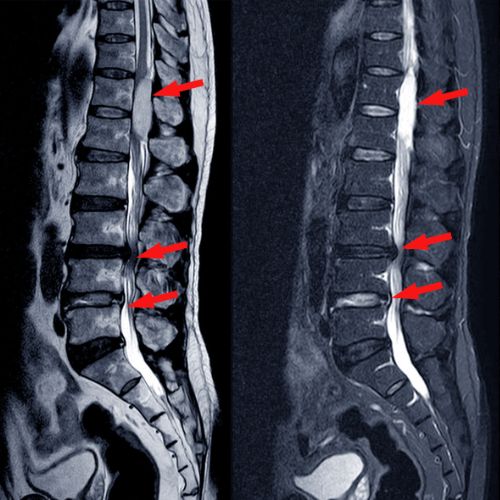

دکتر عادل کیومرثی، با سالها تجربه در زمینه جراحیهای مغز و اعصاب و فوق تخصص ستون فقرات، بهعنوان بهترین جراح مغز و اعصاب در رشت و گیلان در 1404 شناخته میشود. دکتر کیومرثی، با تکیه بر دانش تخصصی و بهروز خود در زمینه جراحیهای مغز، نخاع و ستون فقرات، به بیماران خدماتی تخصصی و مبتنی بر آخرین متدهای پزشکی ارائه میدهند.

این مرکز به ارائه درمانهای پیشرفتهای مانند روش های کم تهاجمی از جمله لیزر و انواع تزریقات جهت کاهش درد و درمان دیسک، جراحیهای مغز، تومورهای مغزی، شانتگذاری مغزی، درمان سردردها و مشکلات ستون فقرات و همچنین درمان سندرم تونل کارپال میپردازد.